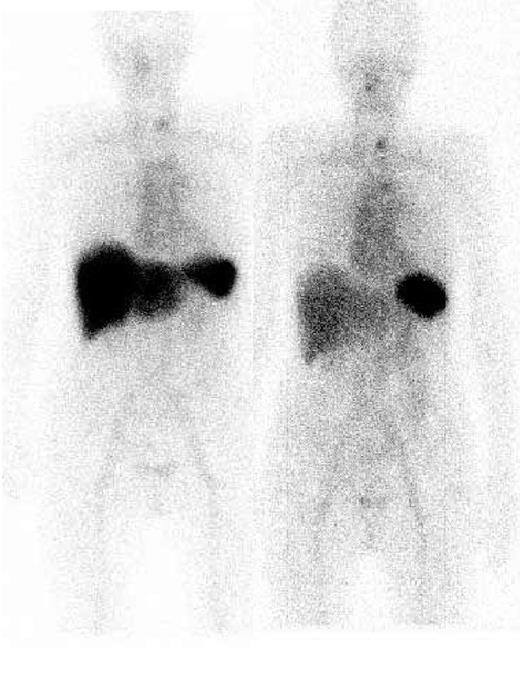

Sixty patients were evaluable for organ responses. Organ responses occurred in 15 (31%) of 48 hematologic responders compared with 1 (5%) hematologic nonresponder (P < .001), a patient who had improvement of serum FLC but less than 50%. Among 11 cases in whom renal function improved, the median decrease in proteinuria from the onset of treatment was 76% (range, 50%-95%). Hepatic function improved in 5 cases, including complete normalization of the liver function tests which included alkaline phosphatase in 2 patients, and the function of other organ systems improved in 6 cases, with some patients showing improvement in more than 1 organ. No patient with end-stage renal failure became dialysis independent following CTD chemotherapy, and no objective cardiac responses were observed. Regression of amyloid deposits by serial SAP scintigraphy was recorded in 16% (7 of 43) of hematologic responders but was not in any nonresponder. Regression of amyloid from the liver (Figure 1) was observed in every patient in whom there was improvement in liver function, whereas regression from the kidneys was only observed in 2 of 11 patients with improvement in renal function, the remainder showing stable deposits.

Serial 123I-labeled anterior whole-body SAP scintigraphy. Visceral amyloid deposits in the spleen and liver pretreatment (left) are shown. Six months after CTD treatment (right), which resulted in a complete clonal response, marked regression of amyloid from the liver was evident.